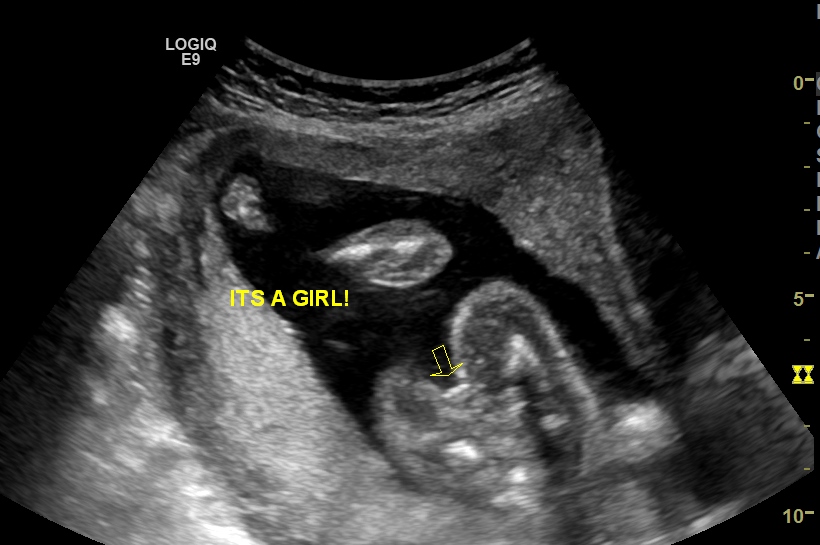

We are still in shock don't think I will believe it till I hold her. Please give me your honest opinions what do you think? After 3 boys I am so excited yet need some reasurance. Thank you for your time.

Attachment 31098